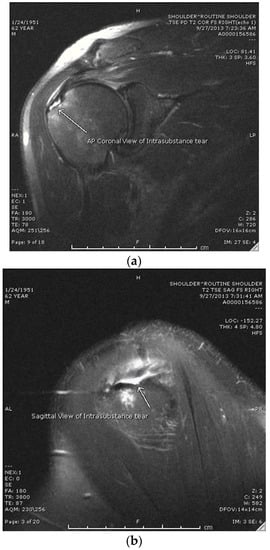

This study is a single-center retrospective cohort study/chart review analyzing functional and clinical outcomes from patients who were treated for an MRI-confirmed high-grade partial rotator cuff tear. Of the 233 charts reviewed, 188 patients were excluded due to having partial rotator cuff tear patters other than an intrasubstance tear (articular- or bursal-sided tears). Patients began receiving treatment in 2015 (when the first PRP injection was performed) through 2016, and data collection concluded at the 2 year mark for the final patients in 2018. The study was conducted in accordance with STROBE guidelines. American Shoulder and Elbow Society Index (ASES) scores and the length of convalescence were used as clinical measurements of success. Length of convalescence was defined as release to work/contact sports. Failure was defined as requiring surgery or an ASES score that did not improve by 15 points (MCID is 15 for ASES) [8,9]. The study population consisted of patients 15 to 80 years of age diagnosed with a high-grade intrasubstance partial rotator cuff tear of <2 cm (with MRI confirmation) who had failed non-operative treatment that included at least one of the following: NSAIDs, corticosteroid injections, or physical therapy, who then decided to undergo a platelet-rich plasma injection as an alternative to surgical intervention (Group 1). After confirmation of an intrasubstance tear via MRI (see Figure 1a,b), patients were presented with the option of a PRP injection vs. arthroscopic rotator cuff repair (RCR).

Figure 1. (a) Coronal T2 image from MRI showing an intrasubstance rotator cuff tear. (b) Sagittal T2 image from MRI showing an intrasubstance rotator cuff tear.